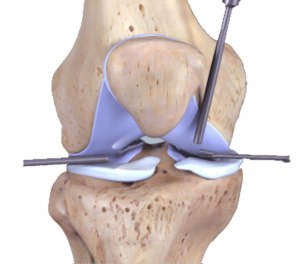

Hastanın yaralanma öyküsü ve şikayetleri değerlendirilir.Fiziki muayenede özel menisküs testleri(mcmurray,apley) ile tanı konulabilir.Menisküs yaralanmalarına genellikle bağ ve kıkırdak yaralanmaları da eşlik ettiği için bu dokulara yönelik değerlendirme yöntemleride uygulanır.Kesin ve ayrıntılı sonuç için MRI görüntüleme ve artroskopi yöntemleri uygulanabilir.

Menisküs yapılarında kan damarı yoktur ve difüzyonla beslenirler.Bu sebeple dokunun kendini tamir yeteneği zordur.Bu yüzden öncelikle cerrahiye ihtiyaç olup olmadığı belirlenir.Cerrahiye gerek varsa cerrahi öncesi ve sonrası rehabilitasyon protokolleri uygulanır.Ameliyatlarda genellikle artroskopi (kapalı) yöntemi kullanılır.Fizik tedavi yöntemleri olarak manuel terapi , germe ve kuvvetlendirme egzesizleri , stabilizasyon egzersizleri uygulanır.Doku iyileşmesini hızlandırıcı ve semptomları azaltıcı elektroterapi uygulamaları da tedavide kullanılır.